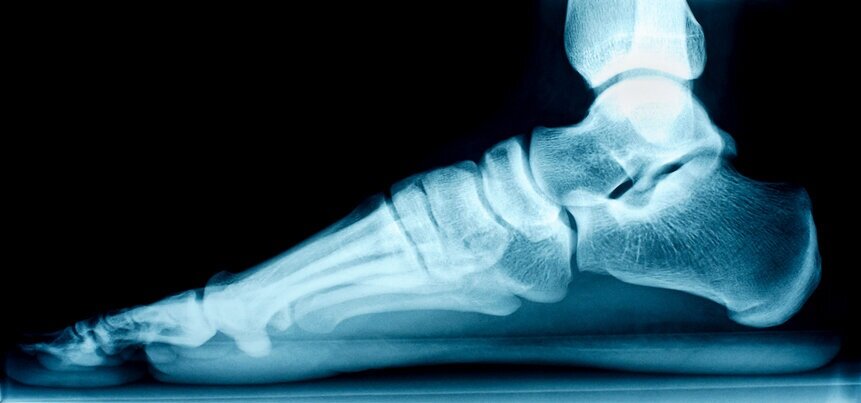

Flat Feet occur when your foot arch collapses and comes into complete contact with the ground. Flat feet are either hereditary or occur because of age. Your podiatrist will examine your foot to diagnose this condition. Treatment may consist of arch supports, foot exercise and over the counter medications. Between 20-30 percent of the population has some degree of flat-footedness. There are few symptoms associated with having flat feet; people experience pain in the mid-foot area and there may be swelling along the inner ankle and arch. People with flat feet may experience hip, knew and lower back pain.

Flat feet occur when your arch descends downward and inward when you walk. They cannot absorb shock and places more stress on your feet, ankles and knees. The cause and treatment differ with age. Children with flat feet tend to resolve itself but adults will have fallen arches forever.

A podiatrist will do a visual exam and some imaging tests to determine the underlying cause of flat feet. The podiatrist will look at your feet while you are standing and will have you wet your foot and step onto a smooth level surface to inspect your footprint. If you have a lot of foot pain, your doctor will order imaging test to help pinpoint the underlying cause.